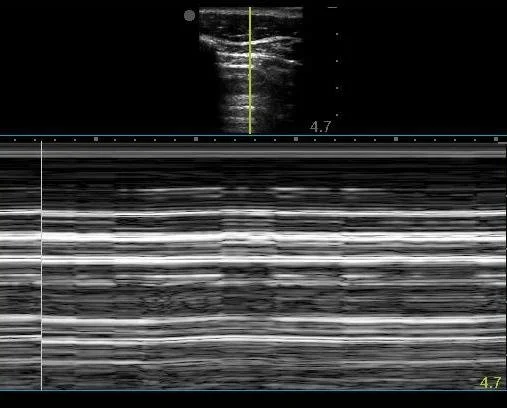

The patient had this interesting ultrasound finding:

This image very clearly demonstrates the “Barcode sign” on M-mode, which indicates absent lung sliding.

Normal lung sliding produces a "Sandy beach" or "Seashore" sign.

The first clip demonstrates no lung sliding on the patient’s right. Note the left side shows normal lung sliding with normal small comet tail artifact.